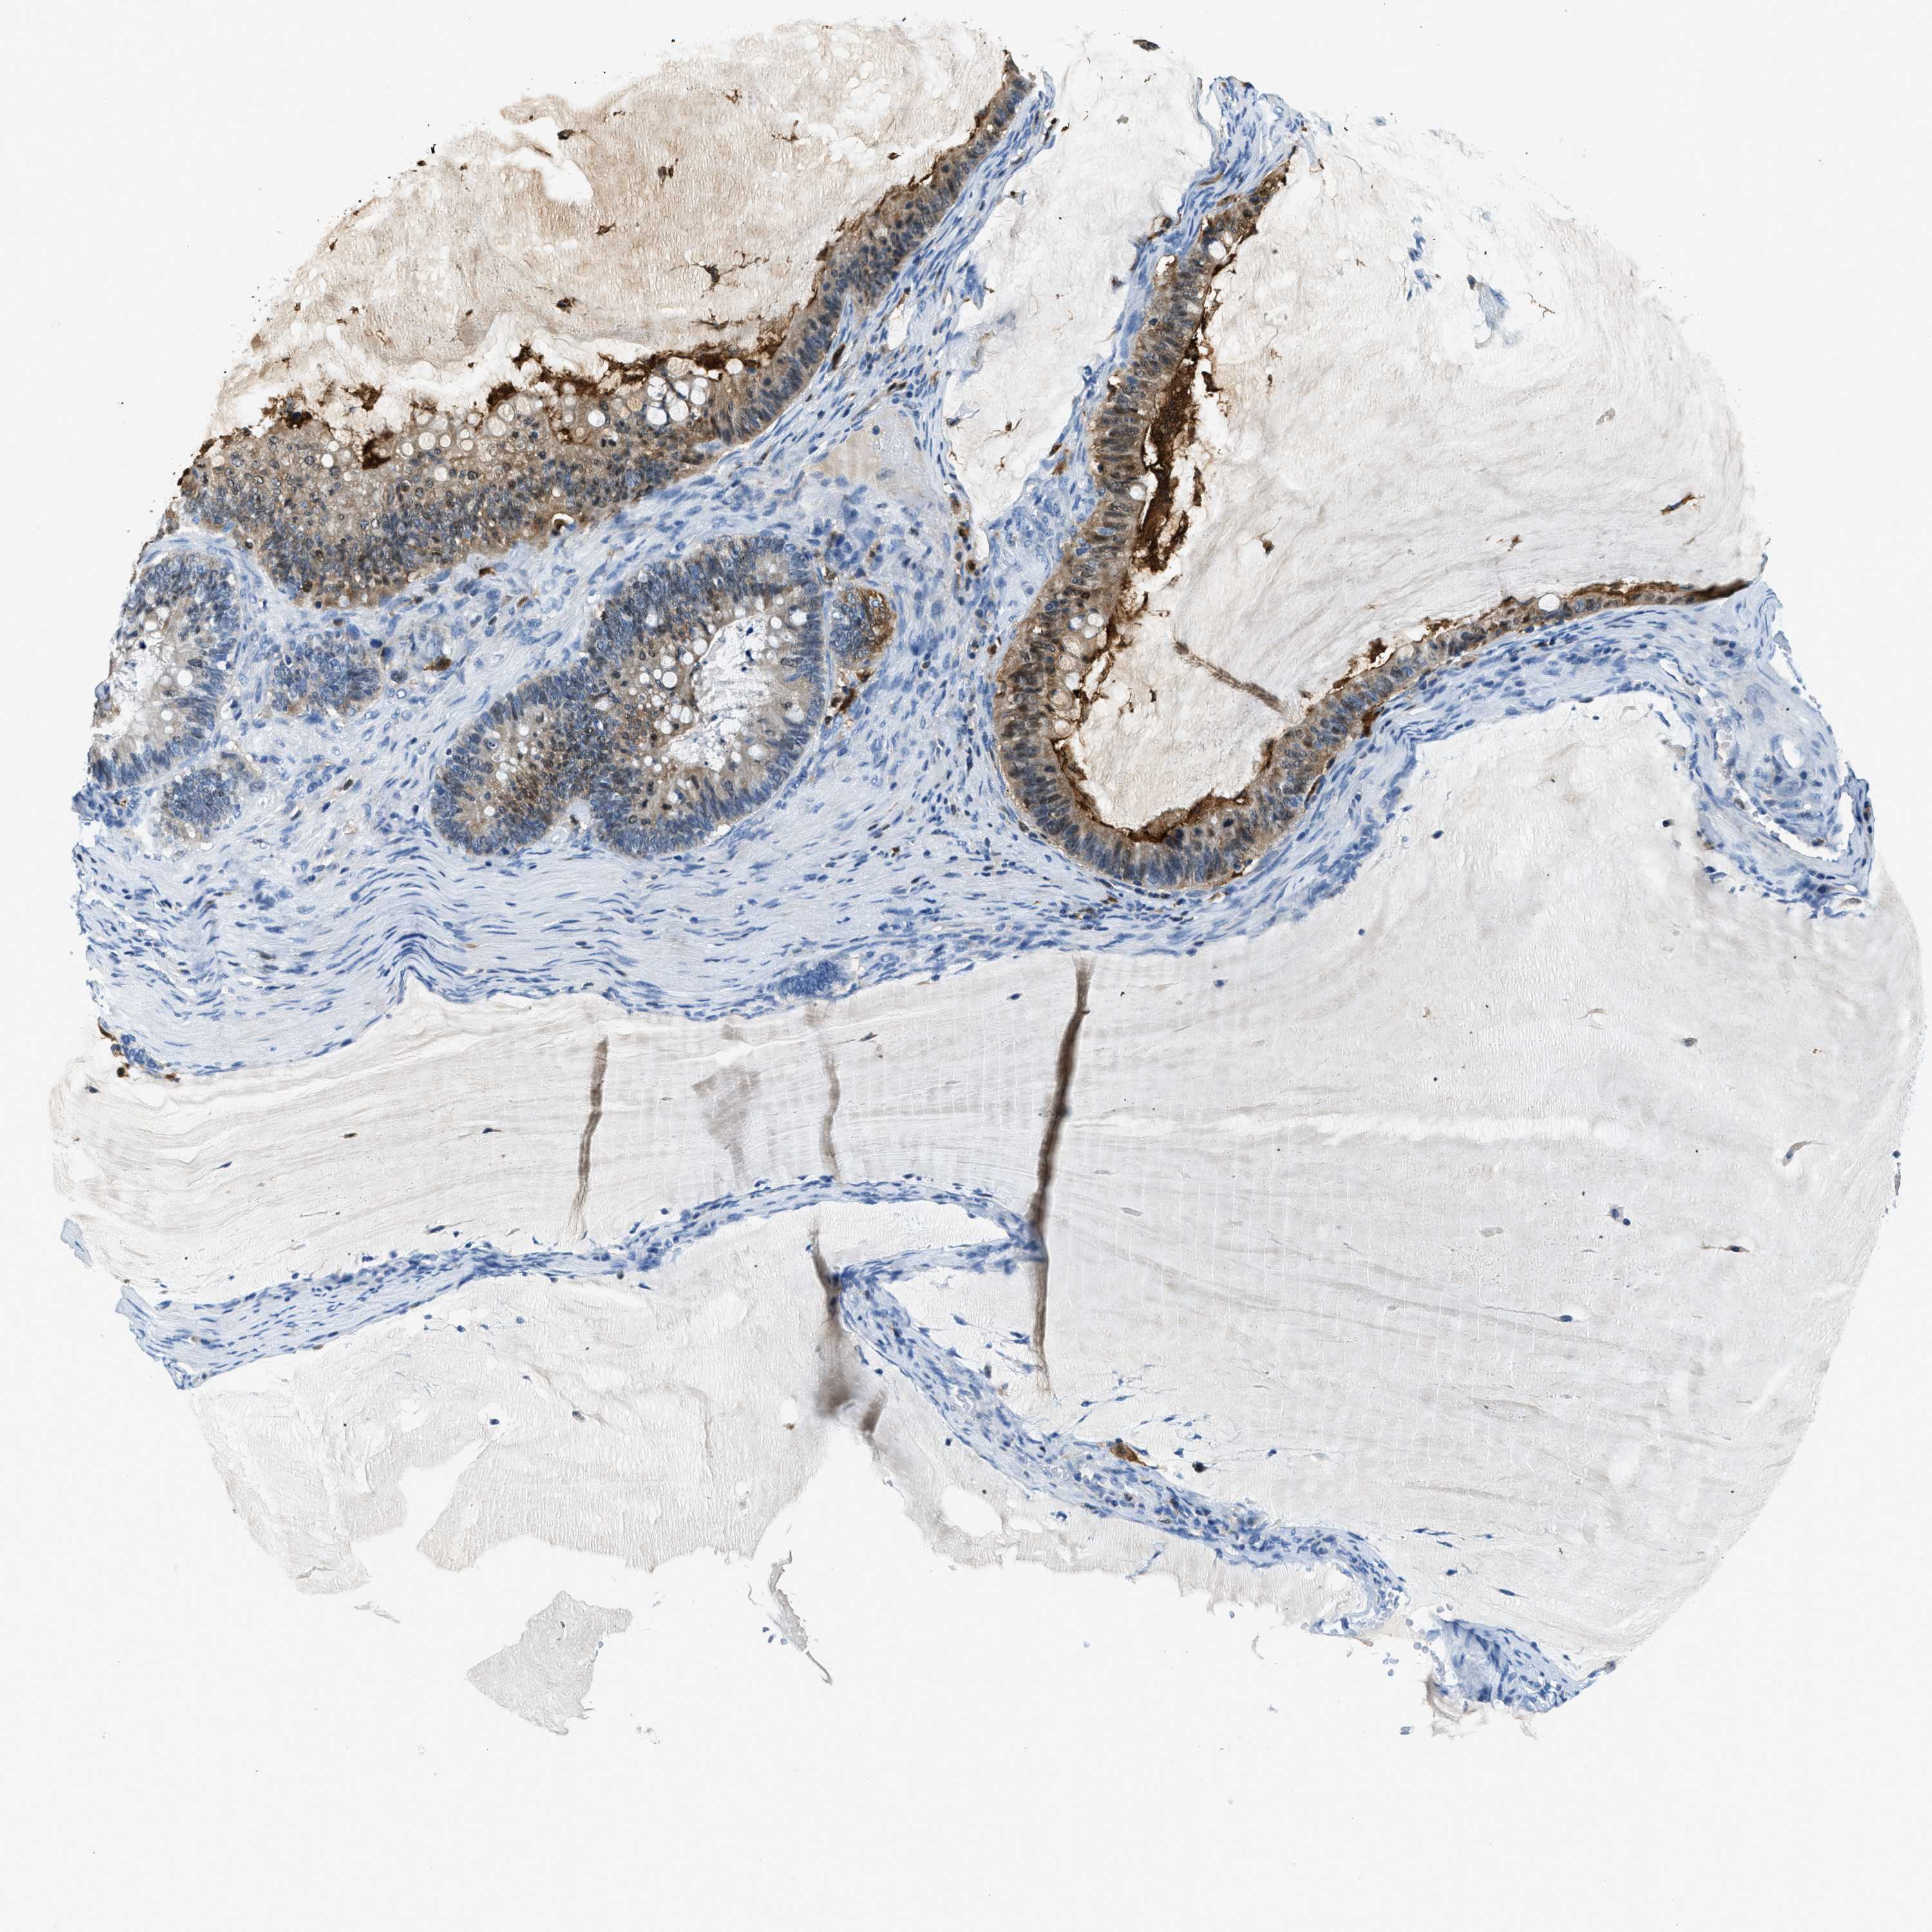

OVARIAN CANCER - Protein expressioni

A mouse-over function shows sample information and annotation data. Click on an image to view it in a full screen mode. Samples can be filtered based on level of antibody staining by selecting one or several of the following categories: high, medium, low and not detected. The assay and annotation is described here.

Note that samples used for immunohistochemistry by the Human Protein Atlas do not correspond to samples in the TCGA dataset.

Antibody stainingi

Antibody staining in the annotated cell types in the current human tissue is reported as not detected, low, medium, or high, based on conventional immunohistochemistry profiling in selected tissues. This score is based on the combination of the staining intensity and fraction of stained cells.

Each image is clickable and will lead to virtual microscopy that enables deeper exploration of all samples and also displays staining intensity scores, fraction scores and subcellular localization as well as patient and tissue information for each sample.

Antibody HPA018843

Antibody HPA019080

Antibody HPA019092

Cystadenocarcinoma, serous, NOS

Carcinoma, endometroid

Cystadenocarcinoma, mucinous, NOS

Carcinoma, NOS